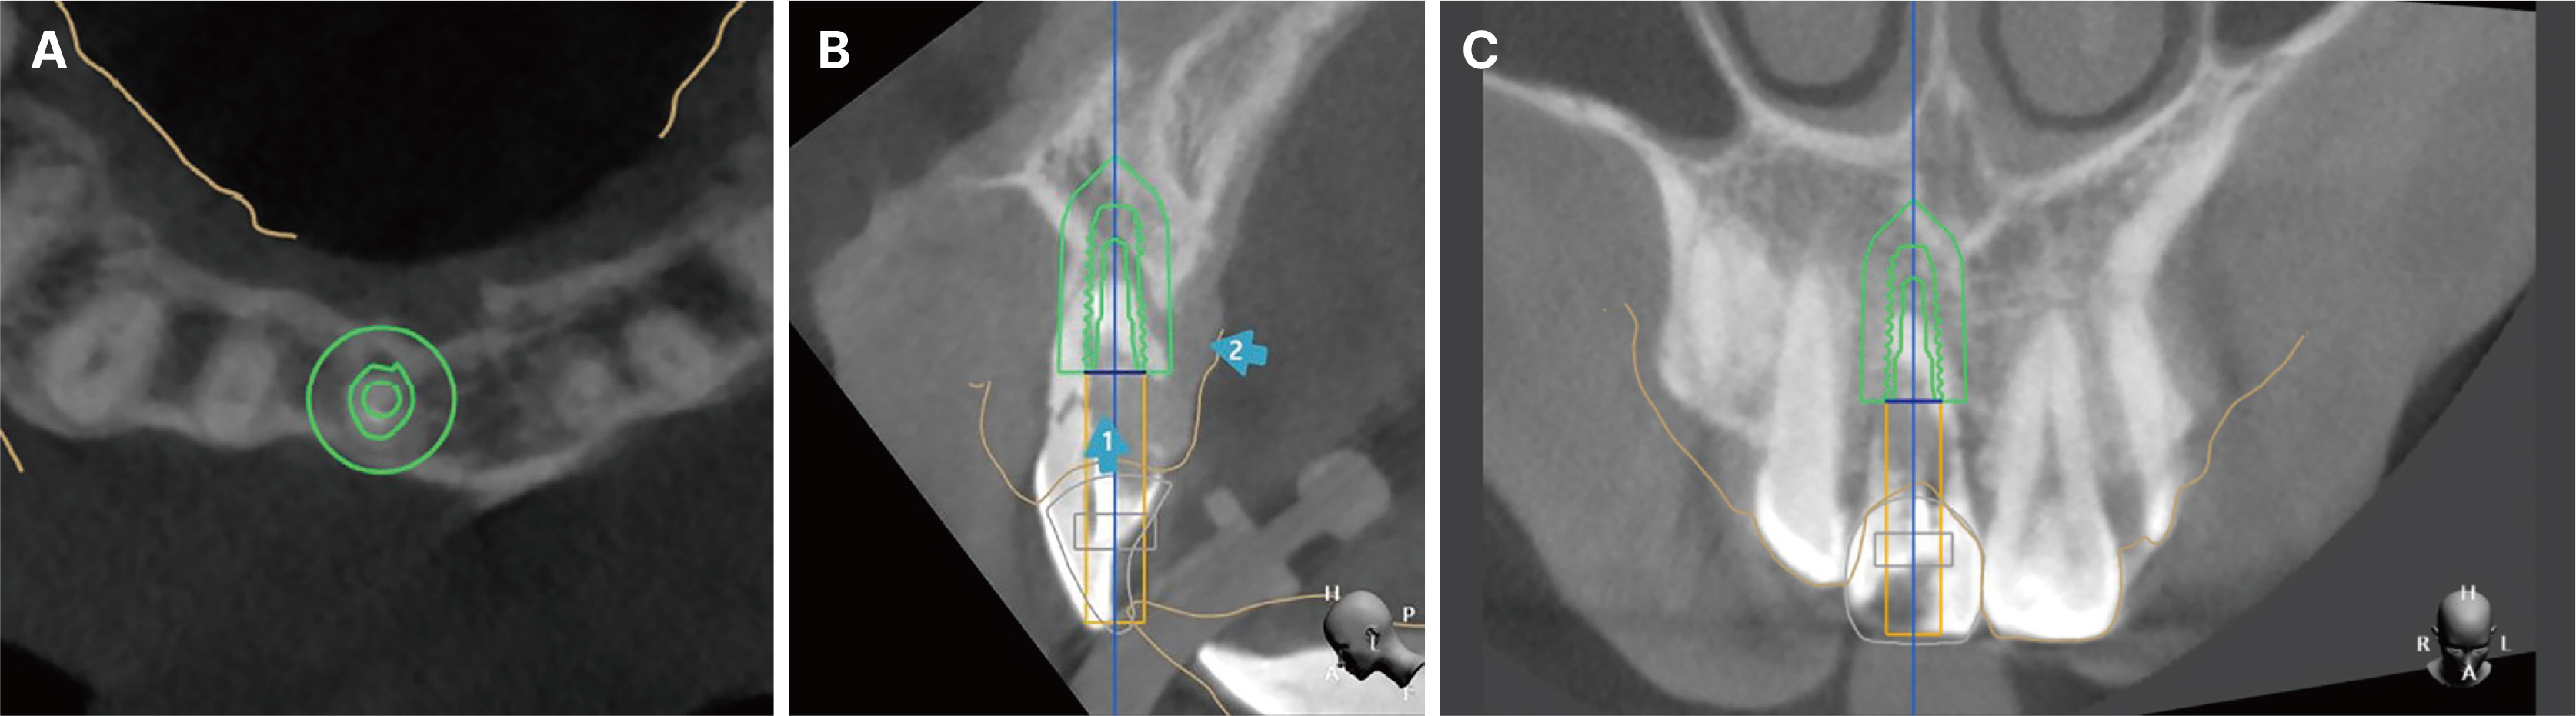

- Immediate implant placement and immediate loading in the anterior maxilla is an effective approach to rapidly address aesthetic demands. To achieve successful outcomes, bone quality, soft tissue condition, and accurate implant positioning are essential factors. For optimal results, procedures such as bone augmentation, precise implant placement, and, when necessary, soft tissue grafting should be considered. Furthermore, provisional restoration play a crucial role in achieving the desired appearance of prosthetic restorations and improving the aesthetics of the soft tissue. By performing soft tissue molding through provisional restoration, an ideal emergence profile can be established, which can be subsequently transferred to the final prosthesis, leading to a functional and aesthetically pleasing restoration. This approach aims to optimize the aesthetic outcomes in the anterior region while preserving the natural contours of the peri-implant soft tissue. In this case, a patient requiring extraction of maxillary anterior tooth underwent immediate implantation and alveolar bone grafting using a guide fabricated in advance from CT data. The patient received a provisional restoration on the same day. Subsequent steps included transitioning from the provisional prosthesis to the definitive prosthesis, ultimately achieving an aesthetically pleasing and functional implant restoration. We report this case to highlight the successful approach to maxillary anterior implant rehabilitation.